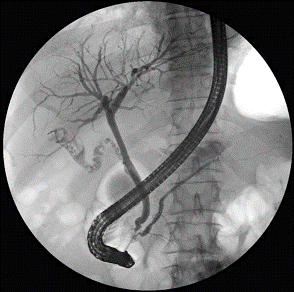

Специальные виды рентгенографии

Холецистография, маммография - рентгенография в

условиях искусственного пневмоторакса, пневмоперитонеума и

пневморет-роперитонеума, париетография, фистулография, некоторые

рентгеноэндоско-пические процедуры и другие являются прерогативой

специализированных учреждений онкологического и иного профиля. Самой

распространенной рент-геноэндоскопической процедурой является эндоскопическая

ретроградная пан-креатохолангиография (ЭРПХГ), при которой через большой

дуоденальный сосочек в холедох и в вирсунгов проток вводится водорастворимое

рентгено-контрастное вещество.Особым разделом специализированной

рентгенодиагностики являются различные виды ангиографии и лимфографии,

показывающие полный или частичный «блок» для прохождения контрастного вещества

в зоне злокачественной опухоли или метастатически пораженного лимфатического

узла.

Холицистография

Маммография ЭРПХГ

Почечная ангиография Лимфография